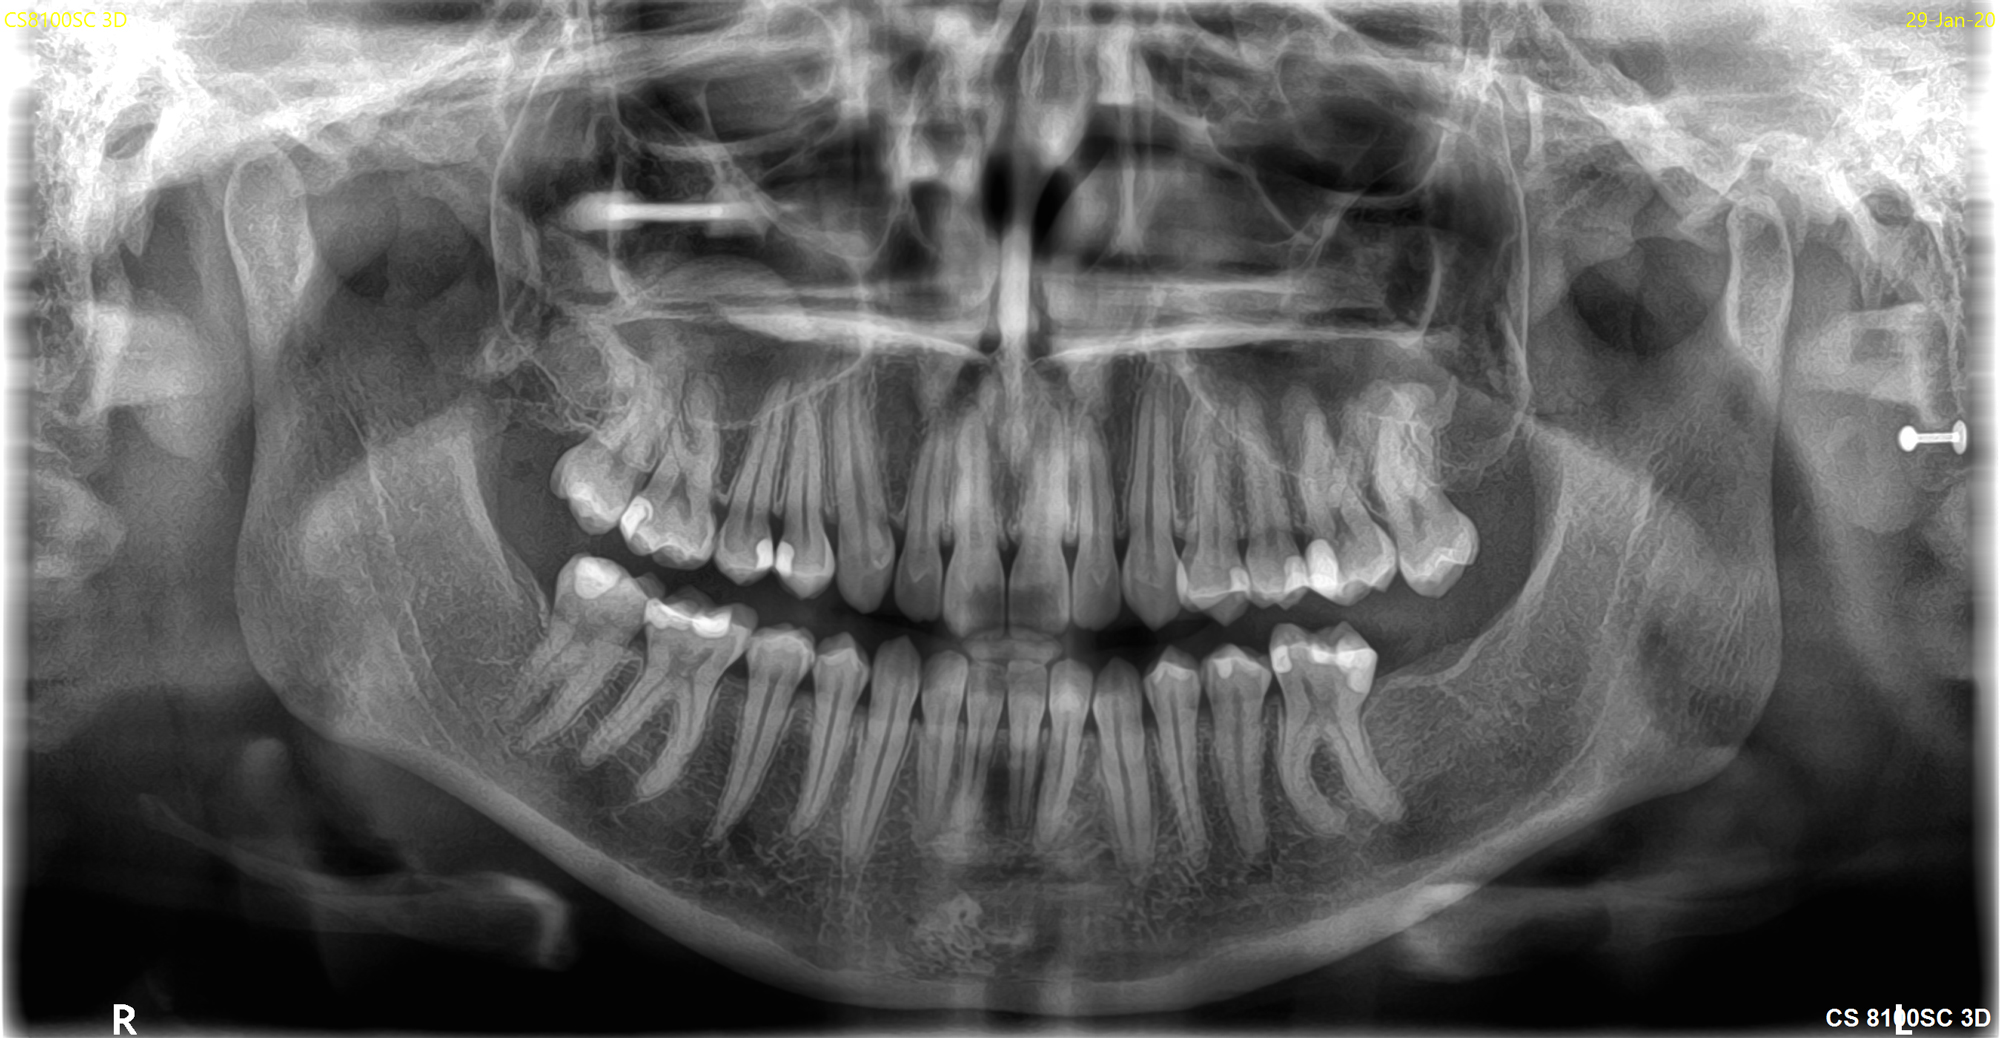

Mοντέλο CS 8200 3D Neo Edition

Το νέο μοντέλο CS 8200 3D Neo Edition της Carestream Dental συνδυάζει Ψηφιακή Πανοραμική με Ογκομετρικό Τομογράφο CBCT, με επιλογή εννέα οπτικών πεδίων και ανάλυση έως 75μm.

Το νέο αυτό μοντέλο αποτελεί την εξέλιξη του ιδιαίτερα πετυχημένου μοντέλου CS 8100 3D.